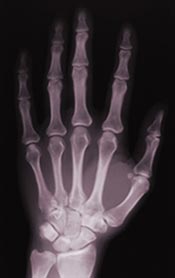

Röntgen didn’t realize it at the time, but that invisible radiation was a type of electromagnetic wave. We can see light waves and we can feel certain other kinds of waves as heat, such as infrared and microwaves. The radiation Röntgen discovered could neither be seen nor felt, but it was there. It gradually became clear that what was happening was that in a cathode-ray tube, electrons, emitted by the cathode, gained speed and struck the anode, releasing their energy as electromagnetic waves. These waves were similar to light waves, but of a much shorter wavelength (one millionth of a centimeter to one ten-billionth of a centimeter). Rontgen found that these waves seemed to pass through materials, such as paper and wood. He also found that they affected photographic film. This meant that he could obtain images of dense materials surrounded by less dense materials, such as bones surrounded by soft tissues.

Röntgen’s x-ray was a major medical breakthrough and was immediately put to work by doctors who used them to diagnose illness and kill harmful tissues, such as cancers. The use of x-rays spread quickly around the globe and in the first decades of the 20th century x-ray machines became standard equipment in hospitals. During wartime, mobile units were placed in the field near battlefields. Many lives were saved by quick diagnosis by x-ray. By the 1950s, however, x-rays were often overused. Some shoe stores even x-rayed feet as a way of measuring shoe size. Gradually it became clear that the power of the x-ray was to be taken seriously—x-rays can damage living tissue. As awareness of the potential danger of overexposure to x-ray radiation grew, use of x-raying became limited to medical situations and precautions, such as the lead apron you wear at the dentist’s, were taken.